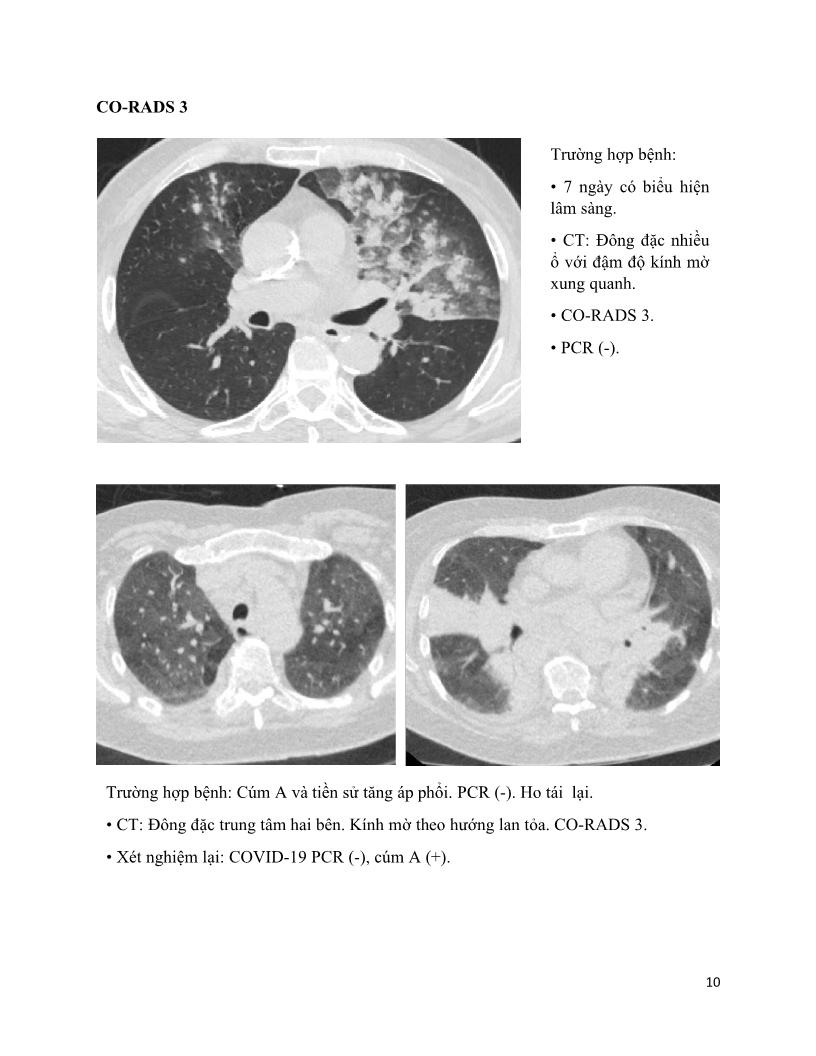

Hướng dẫn CT Ngực phổi chuẩn Covid-19